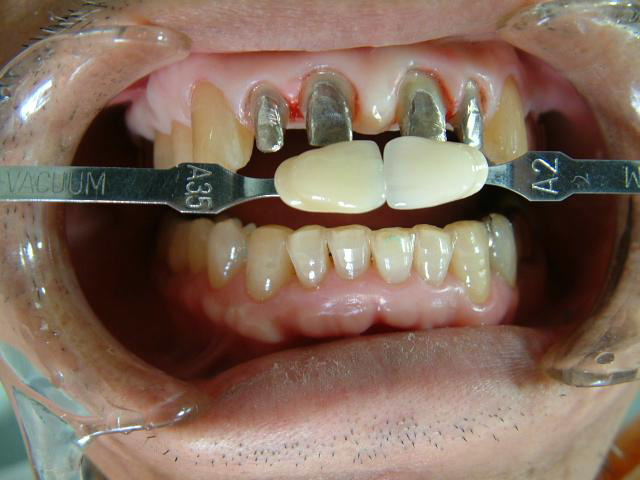

※前突した形態と色を修正したケース

患者さんの希望として

☆出歯を直して内側に入れて欲しい

☆綺麗な歯にして欲しい

☆1.1の間の小ダミーを取り除いて審美的に

美しい歯を作り上げることができるのか?

技工士からの回答として

☆下顎前歯の切端を削って頂ければ

2〜2を内側に入れて審美的にも納得して

頂ける補綴物が出来ると思われます。

☆テックにて患者さんが満足されるか確認してから

最終補綴物に移行しましょう

☆2.2の歯の幅を広げ、1.1の幅を狭くし

全体のバランスを取り作りたいと思います

☆1〜1の間の歯間空隙部分が不自然にならない

よう歯肉模型にて確認しながら製作します |